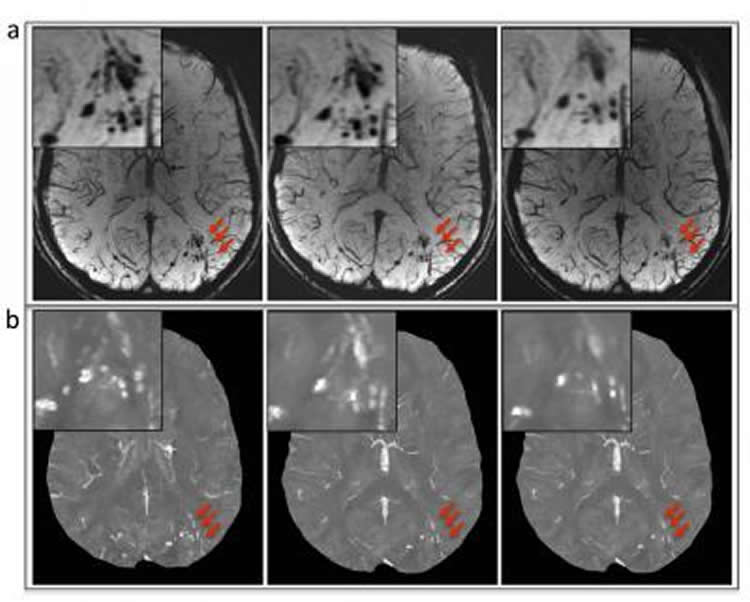

The study also supports previous claims that using susceptibility-weighted imaging to evaluate brain injury patients may be more effective than conventional MRI. In this study’s capacity, using susceptibility-weighted imaging resulted in detecting significantly more microhemorrhages due to a higher spatial resolution and signal, with 77 percent of cerebral microhemorrhages appearing more evident through susceptibility-weighted imaging when compared to conventional MRI.

To detect cerebral microhemorrhages in military service members with chronic traumatic brain injury by using susceptibility-weighted magnetic resonance (MR) imaging. The longitudinal evolution of microhemorrhages was monitored in a subset of patients by using quantitative susceptibility mapping.

Among the 603 patients, cerebral microhemorrhages were identified in 43 patients, with six excluded for further analysis owing to artifacts. Seventy-seven percent (451 of 585) of the microhemorrhages on susceptibility-weighted images had a more conspicuous appearance than on gradient-recalled-echo images. Thirteen of the 37 patients underwent follow-up imaging examinations. In these patients, a smaller number of microhemorrhages were identified at follow-up imaging compared with baseline on quantitative susceptibility maps (mean ± standard deviation, 9.8 microhemorrhages ± 12.8 vs 13.7 microhemorrhages ± 16.6; P = .019). Quantitative susceptibility mapping–derived quantitative measures of microhemorrhages also decreased over time: −0.85 mm3 per day ± 1.59 for total volume (P = .039) and −0.10 parts per billion per day ± 0.14 for mean magnetic susceptibility (P = .016).

The number of microhemorrhages and quantitative susceptibility mapping–derived quantitative measures of microhemorrhages all decreased over time, suggesting that hemosiderin products undergo continued, subtle evolution in the chronic stage.